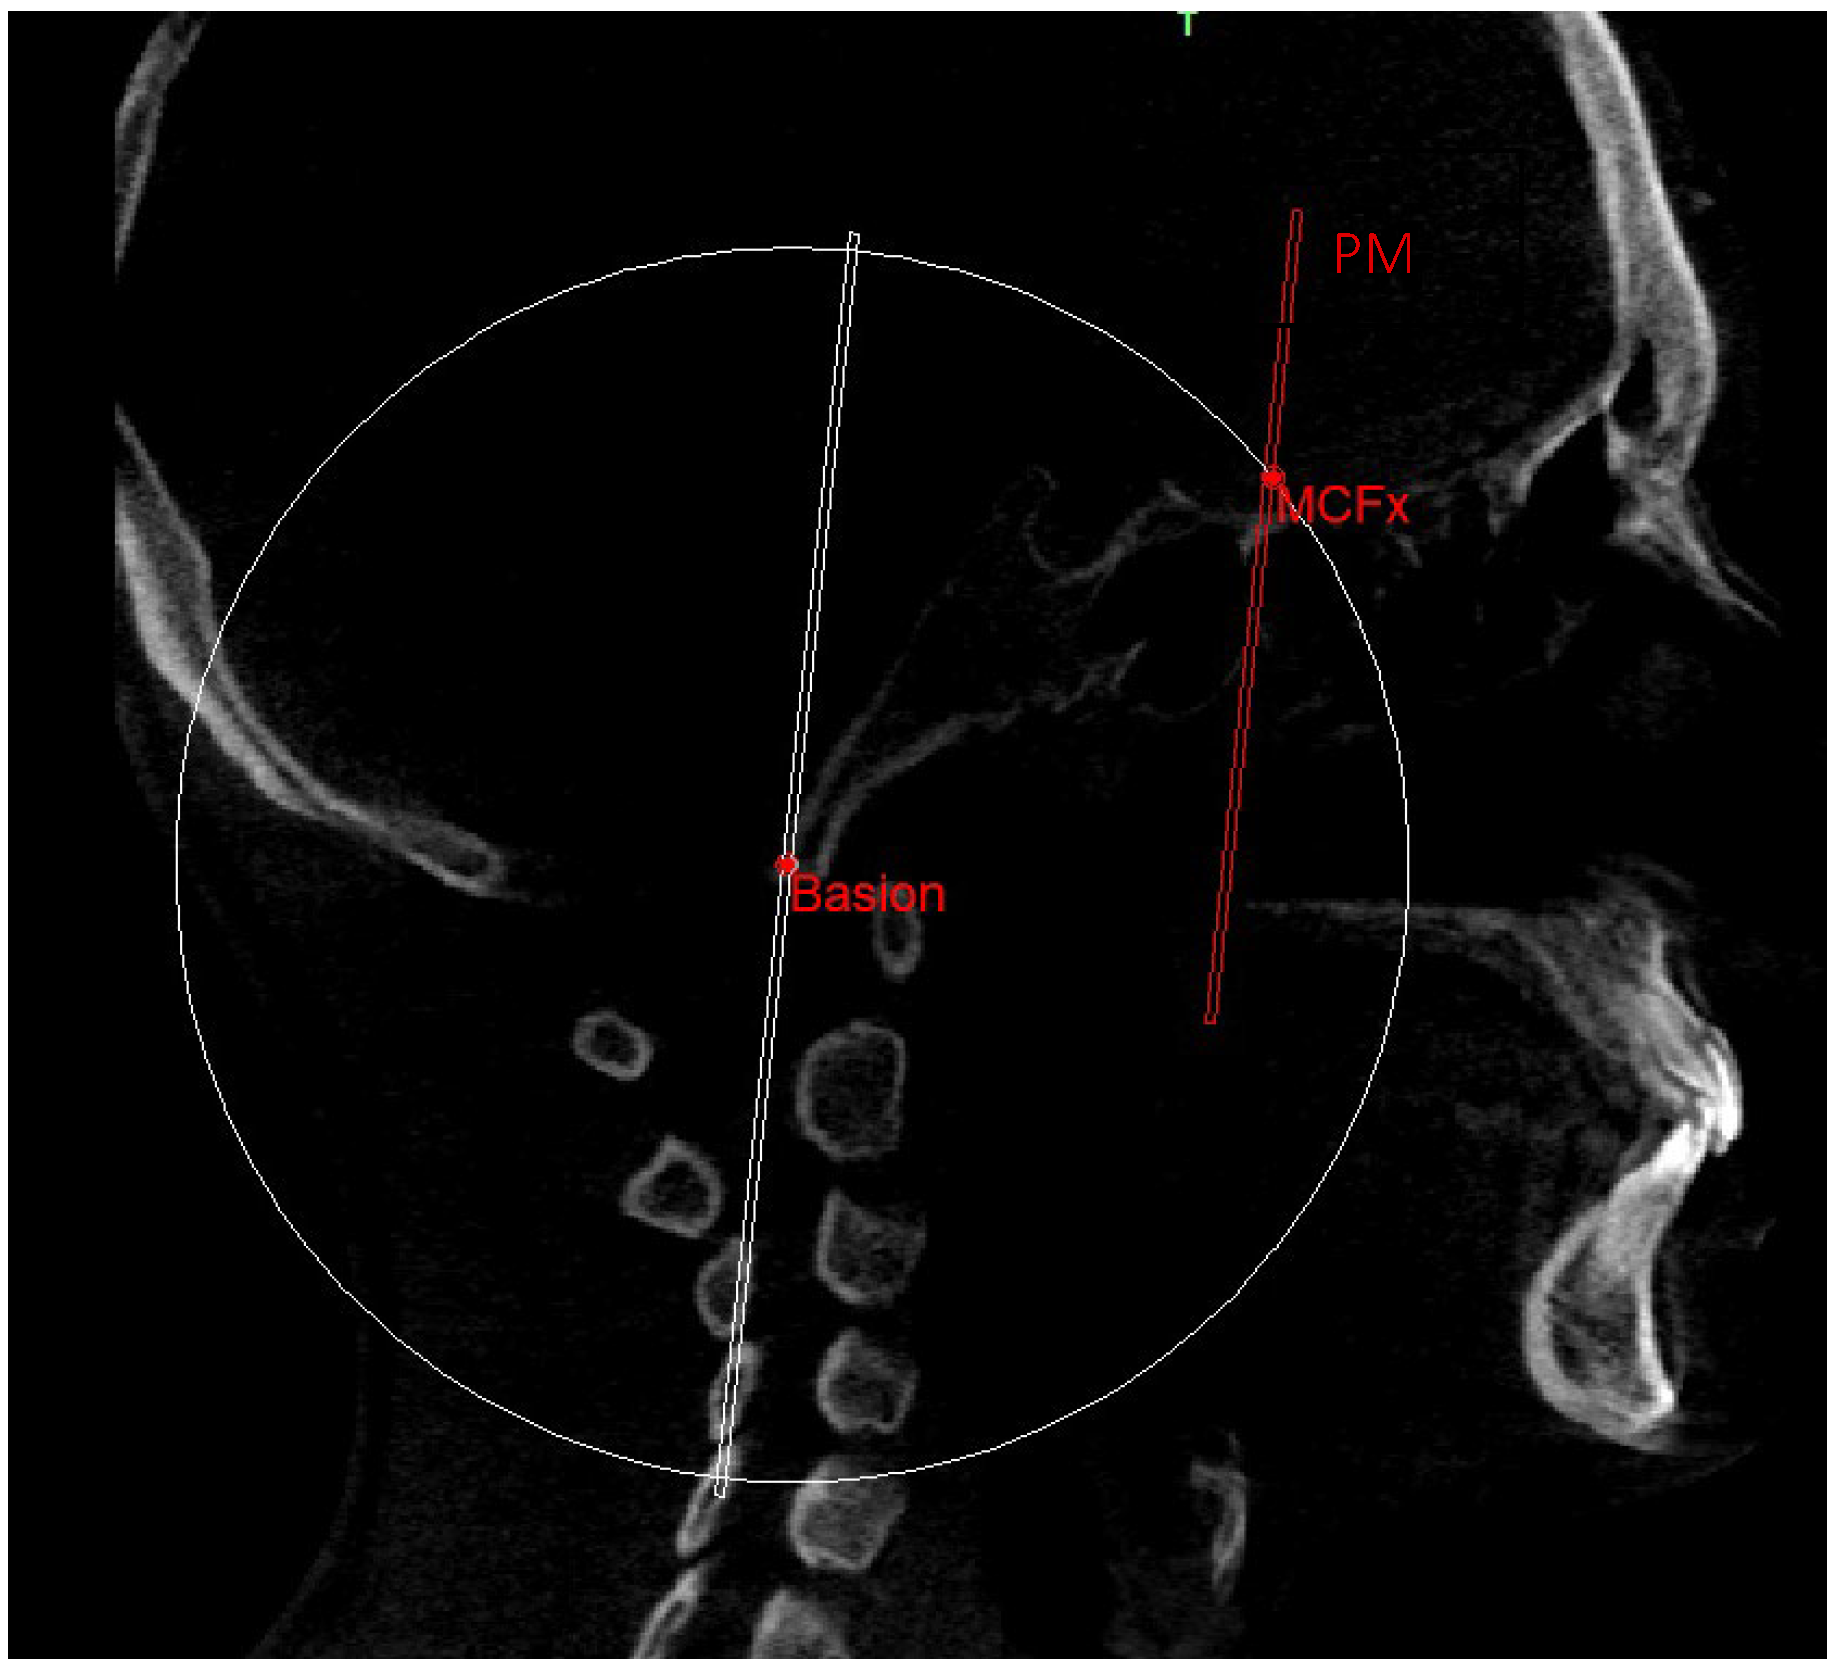

The construction of the neutral track [10] began by drawing a sphere with its center in the Ba point and the radius corresponding to the segment that joins the Ba to the middle point MCF (MCFx) (Figure 8). From this sphere in the sagittal view, we obtained a circumference necessary to identify the neutral sphenoethmoidal junction point (SEn).

Figure 8. Sphere with radius from Ba to MCFx.